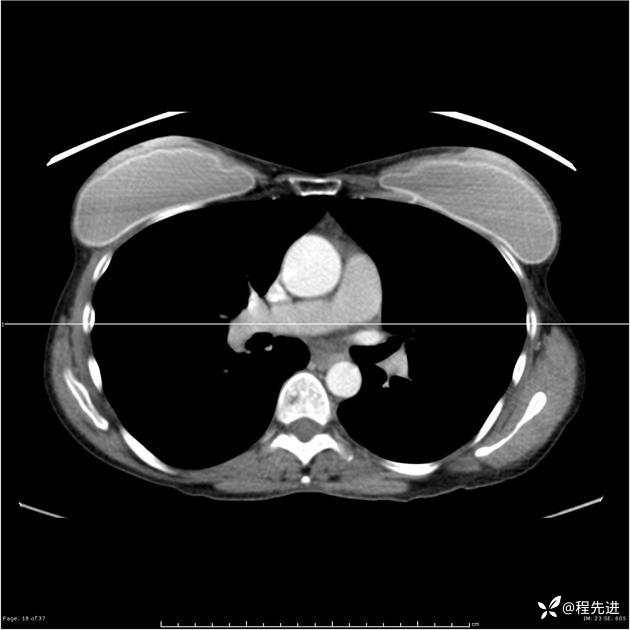

病例女,53岁,气管、左主支气管、下叶支气管内结节,乳头状瘤?期待你的精彩解读

女,53岁

乳头状瘤?